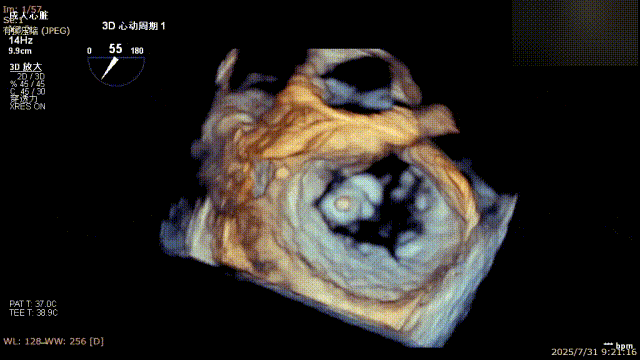

术前完善经食管超声评估,提示该患者双房大,二尖瓣重度反流4+伴后叶脱垂、后叶部分腱索断裂。根据评估结果,心脏大血管外科王安彪主任团队制定了周密的手术方案:植入一枚夹合器,钳夹P1区反流最大处,尽可能夹持全部后叶脱垂瓣叶组织,后续根据术中实时残余分流和跨瓣压差等指标,并依据实时超声监测调整治疗策略。

三维评估

二尖瓣P1脱垂偏心性返流